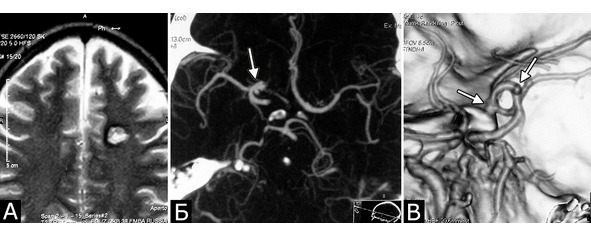

У 5-х больных с клинически проявившимися каверномами в ходе обследования выявлены бессимптомные артериальные аневризмы передних отделов вилизиева круга (рис. 3). Обращал на себя внимание тот факт, что в 4-х случаях аневризмы были множественными.

Рис. 3. Б-ной К-ов, 37 лет. Сочетанная сосудистая патология мозга: КМ глубинных отделов лобной доли слева (А – МРТ, режим Т2); две аневризмы ВСА справа (Б, В – СКТ-АГ, аневризмы указаны стрелками). Течение болезни: за 6 месяцев до поступления перенес два генерализованных судорожных припадка. При МРТ выявлена КМ лобной доли слева, которая послужила причиной припадков. При СКТ-АГ выявлены две аневризмы ВСА справа (случайная находка). Лечение: 1-ая операция – клипирование двух аневризм ВСА справа. 2-ая операция – удаление каверномы левой лобной доли